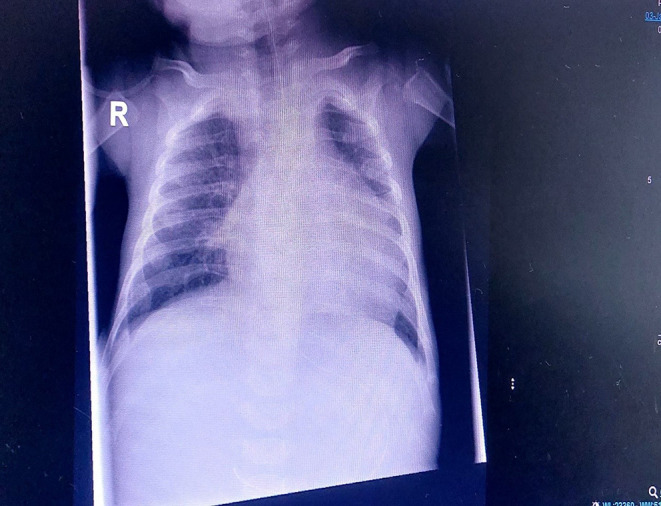

Case presentation: This report describes a 3-month-old female diagnosed with congenital AML, characterized by mixed lineage leukemia (MLL) gene rearrangement. The patient presented with severe complications, including typhlitis, abscess, seizures, and pericardial effusion.